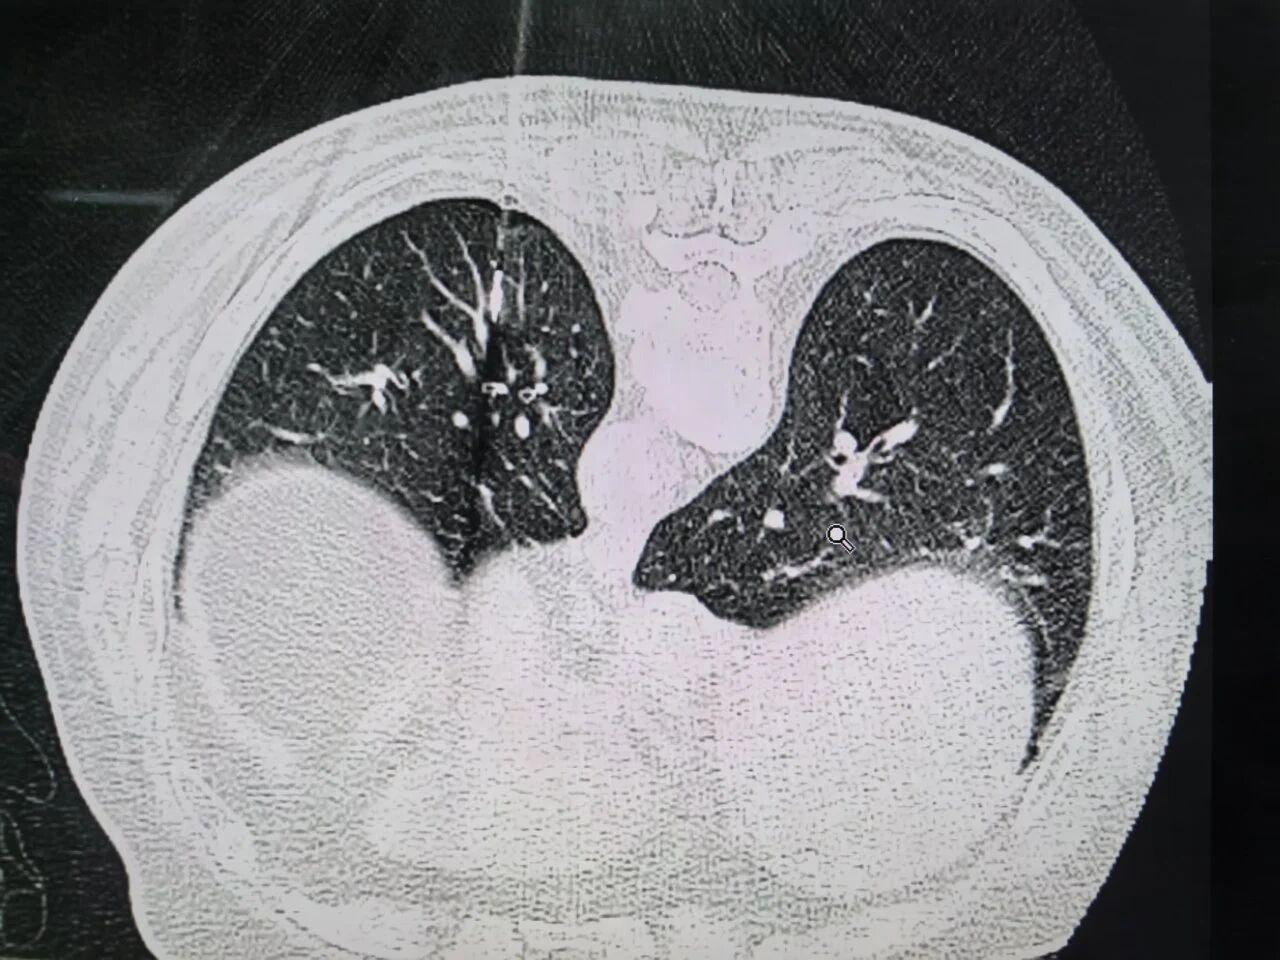

该患者一年前体检发现肺部多发结节,随访期间病灶持续增大,其中左肺上叶部分实性病灶达2.5cm,下叶9mm,病灶位置深。

手术中,河南省人民医院胸外科主治医师张全在CT精准定位下,以1-2mm穿刺针孔完成微波消融,35W功率使病灶局部温度升至60~150℃,实现肿瘤细胞凝固性坏死,即时CT显示消融范围达标;随后主任医师李基伟主刀单孔胸腔镜手术,完成肺叶切除与淋巴结清扫。